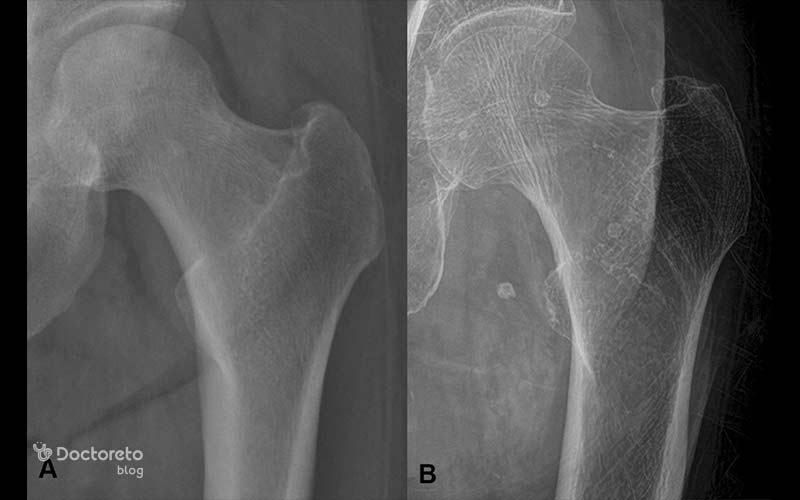

عکس استخوان سالم و دچار پوکی استخوان

برای این که بتوانید درک بهتر از پوکی استخوان داشته باشید، بهتر است عکس استخوان سالم را با عکس استخوانهایی که دچار پوکی استخوان شدهاند، مقایسه کنید. در عکس استخوانهای سالم، بافت استخوانی متراکم است و فضاهای خالی کمی در آن دیده میشود. اما به نسبت این که شدت بیماری چقدر است، در عکس پوکی استخوان شاهد علائم پوکی استخوان و کاهش تراکم بافت استخوانی هستیم و یک بافت متخلخل (سوراخدار) را مشاهده میکنیم.

استخوان سالم الگویی از صفحات استخوانی قوی و بههمپیوسته را نشان میدهد. این در حالی است که در پوکی استخوان، بخش عمده این صفحات استخوانی از بین میروند و باقی مانده بافت استخوانی، بسیار ضعیف و کمتراکم است. بافت استخوانی در پوکی استخوان به صورت میلههای ضعیفی است که هیچ کمکی به استحکام استخوانها نمیکنند. هر چقدر که بیماری شدیدتر باشد، ساختارهای محدودتر و ضعیفتری را در عکسهای پوکی استخوان میبینیم.

The normal bone shows a pattern of strong interconnected plates of bone. Much of this bone is lost in osteoporosis and the remaining bone has a weaker rod-like structure.

استخوان طبیعی الگویی از صفحات استخوانی قوی و بههمپیوسته را نشان میدهد. بخش زیادی از این استخوان در پوکی استخوان از بین میرود و استخوان باقیمانده ساختار میلهایشکل ضعیفتری دارد.